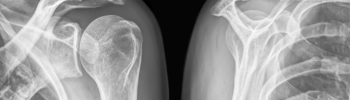

Diagnóstico del Síndrome Subacromial - Tratamiento en FisioClinics Palma